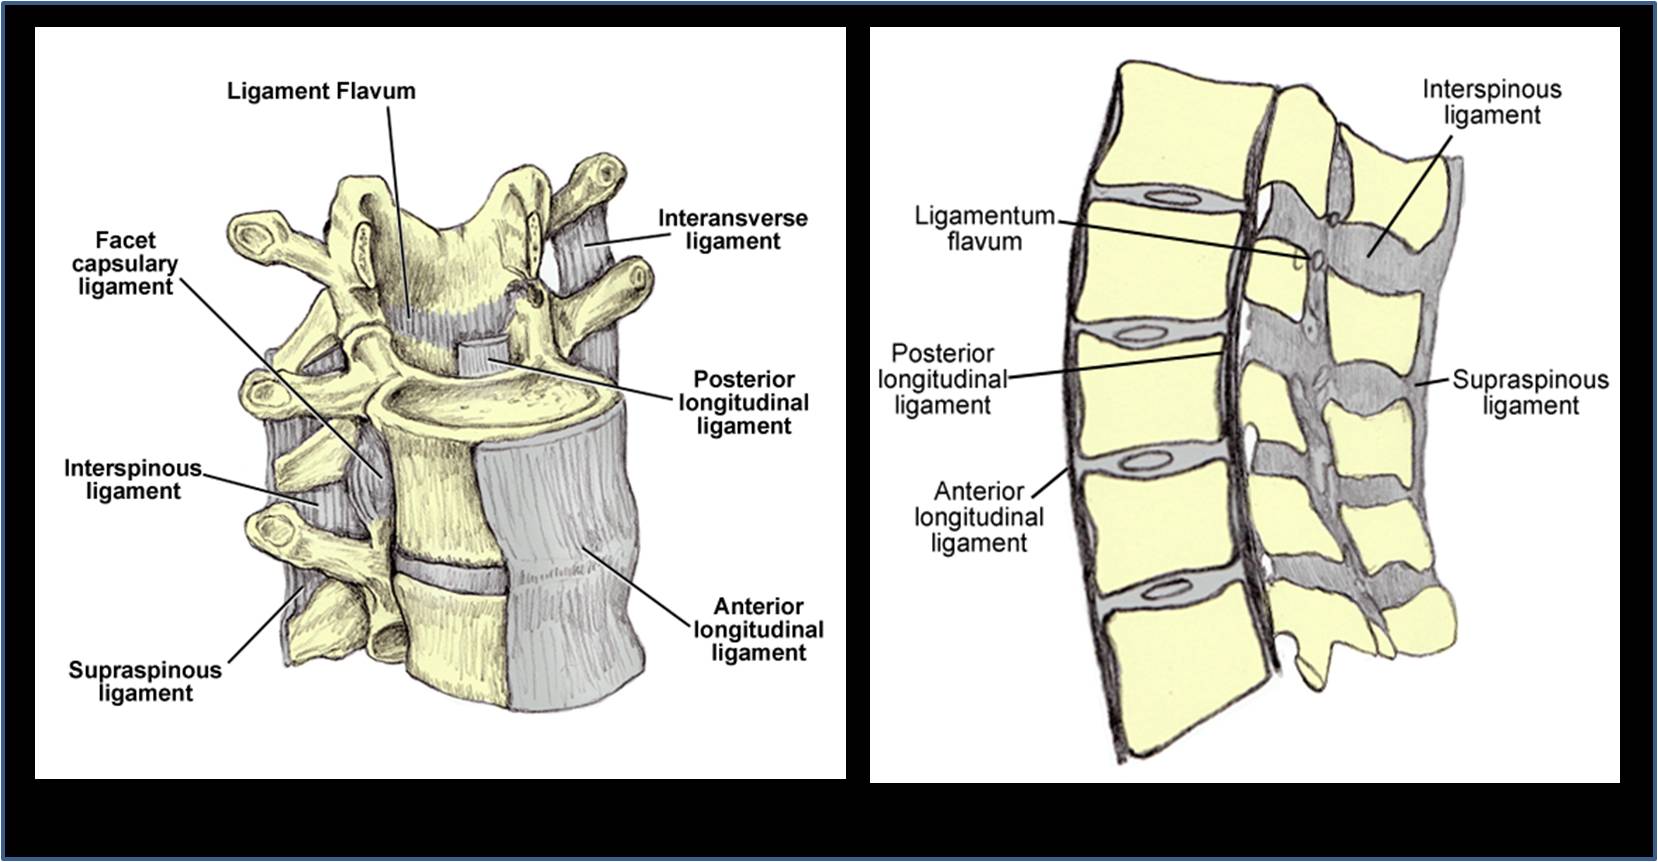

Pure Health - Anatomy 101 - Supraspinous ligament and interspinous ligament 📚 The supraspinous ligament and interspinous ligament work together to limit flexion of the spine by limiting separation of the spinous

DOCS - The interspinous ligament is located between the spinous processes of adjacent vertebrae in the spine. It extends from the base of one spinous process to the apex of the next,

The vertebral column usually contains three curves. The cervical and lumbar curves are convex anteriorly, and the thoracic curve is convex posteriorly. These curves, together with gravity, barricity of the local anesthetic,